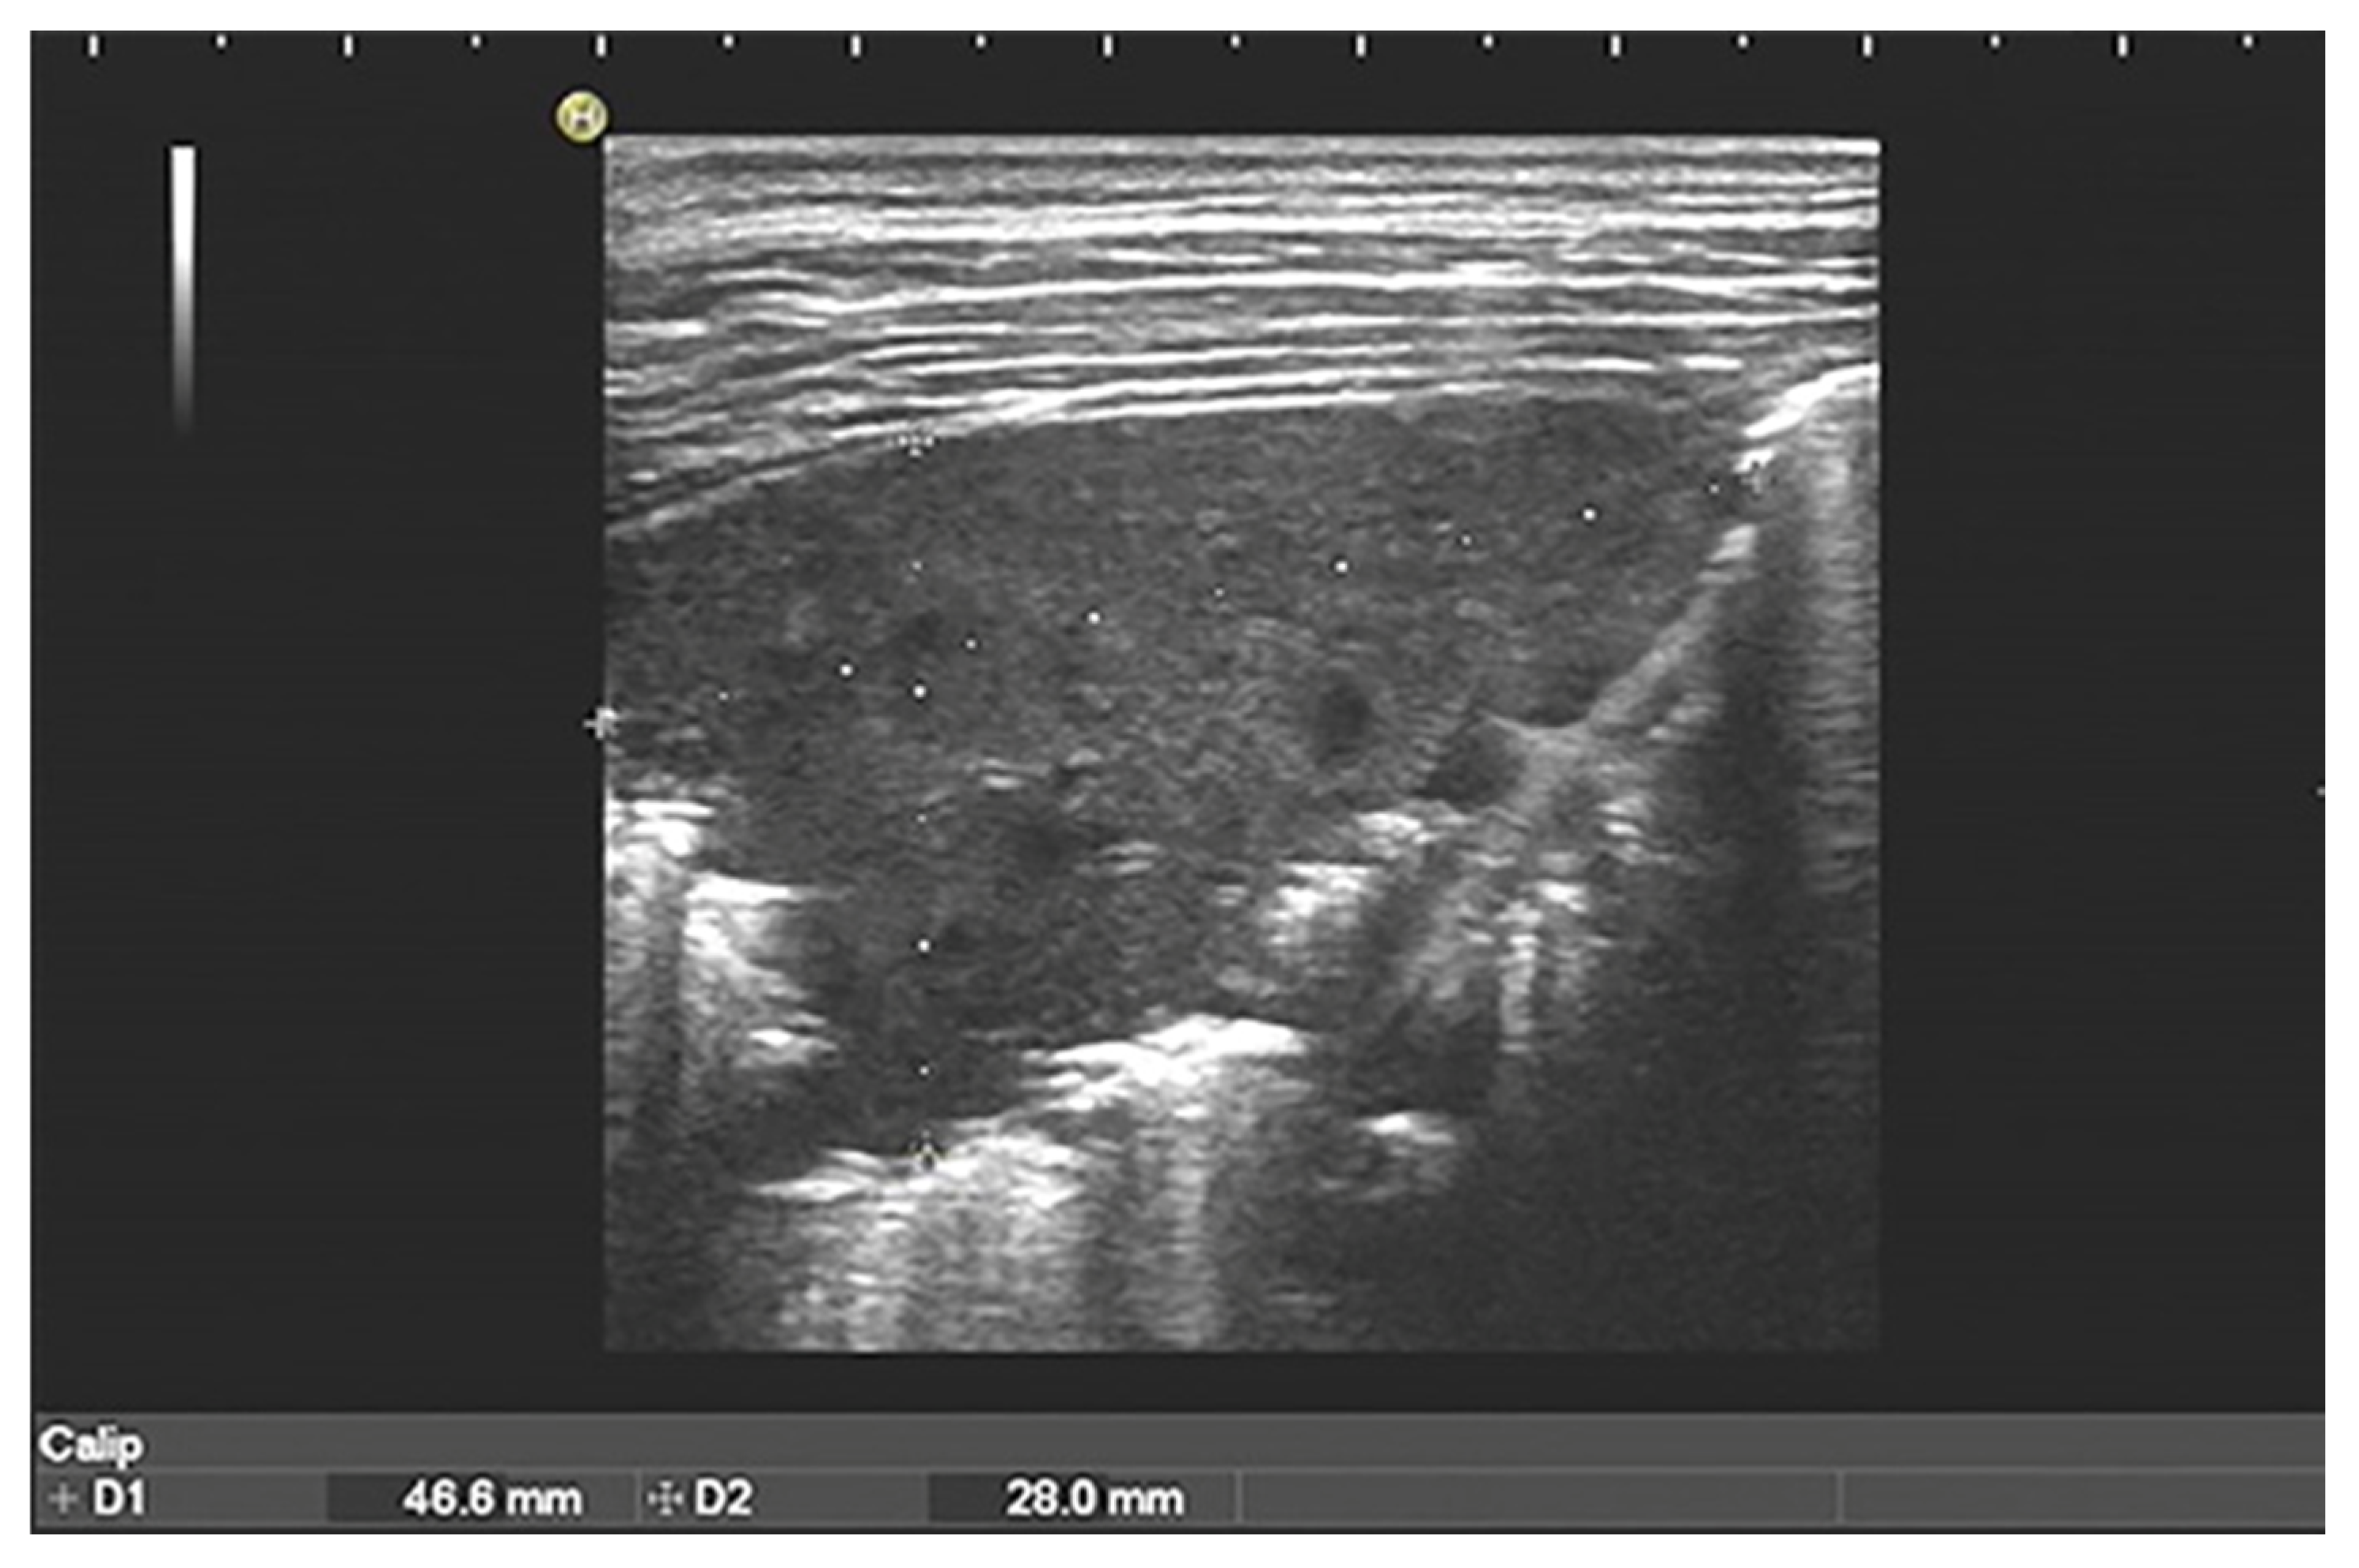

| Consolidation | Area in which lung tissue is de-aerated with density similar to parenchymal tissues [23] |

| Atelectasis | Type of consolidation shown as hyperechogenic tissue structure visualized as solid parenchyma with static air bronchogram [11,24] |

| Cavitation | Solid, hypoechoic, heterogeneous lesions with sharp lobulated margins [11,25] |

| Pleural effusion | Hypo- or anechogenic structure, delineated by the chest wall and the diaphragm [11,26] |